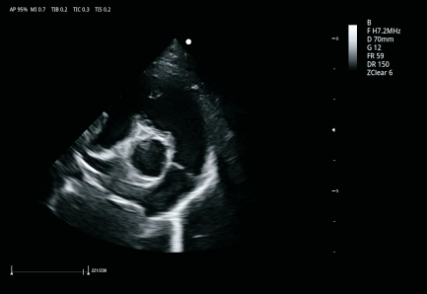

VU60搭载了全新的焕影成像技术平台,采用uSeed全新的CPU+GPU+FPGA硬件架构,多核并行处理技术,搭载高性能单晶体探头和复合晶体探头,可提供更宽带宽、更好穿透力和分辨率的超声影像,精准高效,全面提升临床诊断信心。

卓越的图像质量